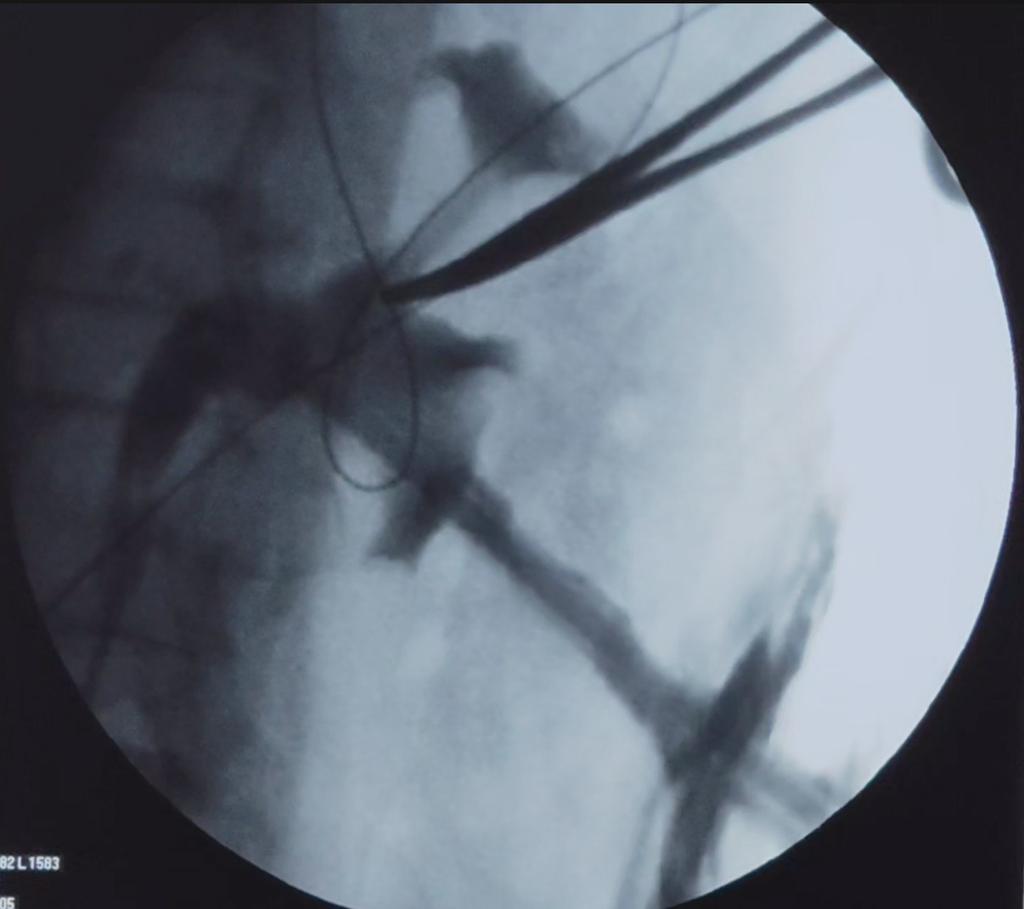

🔹 PCNL